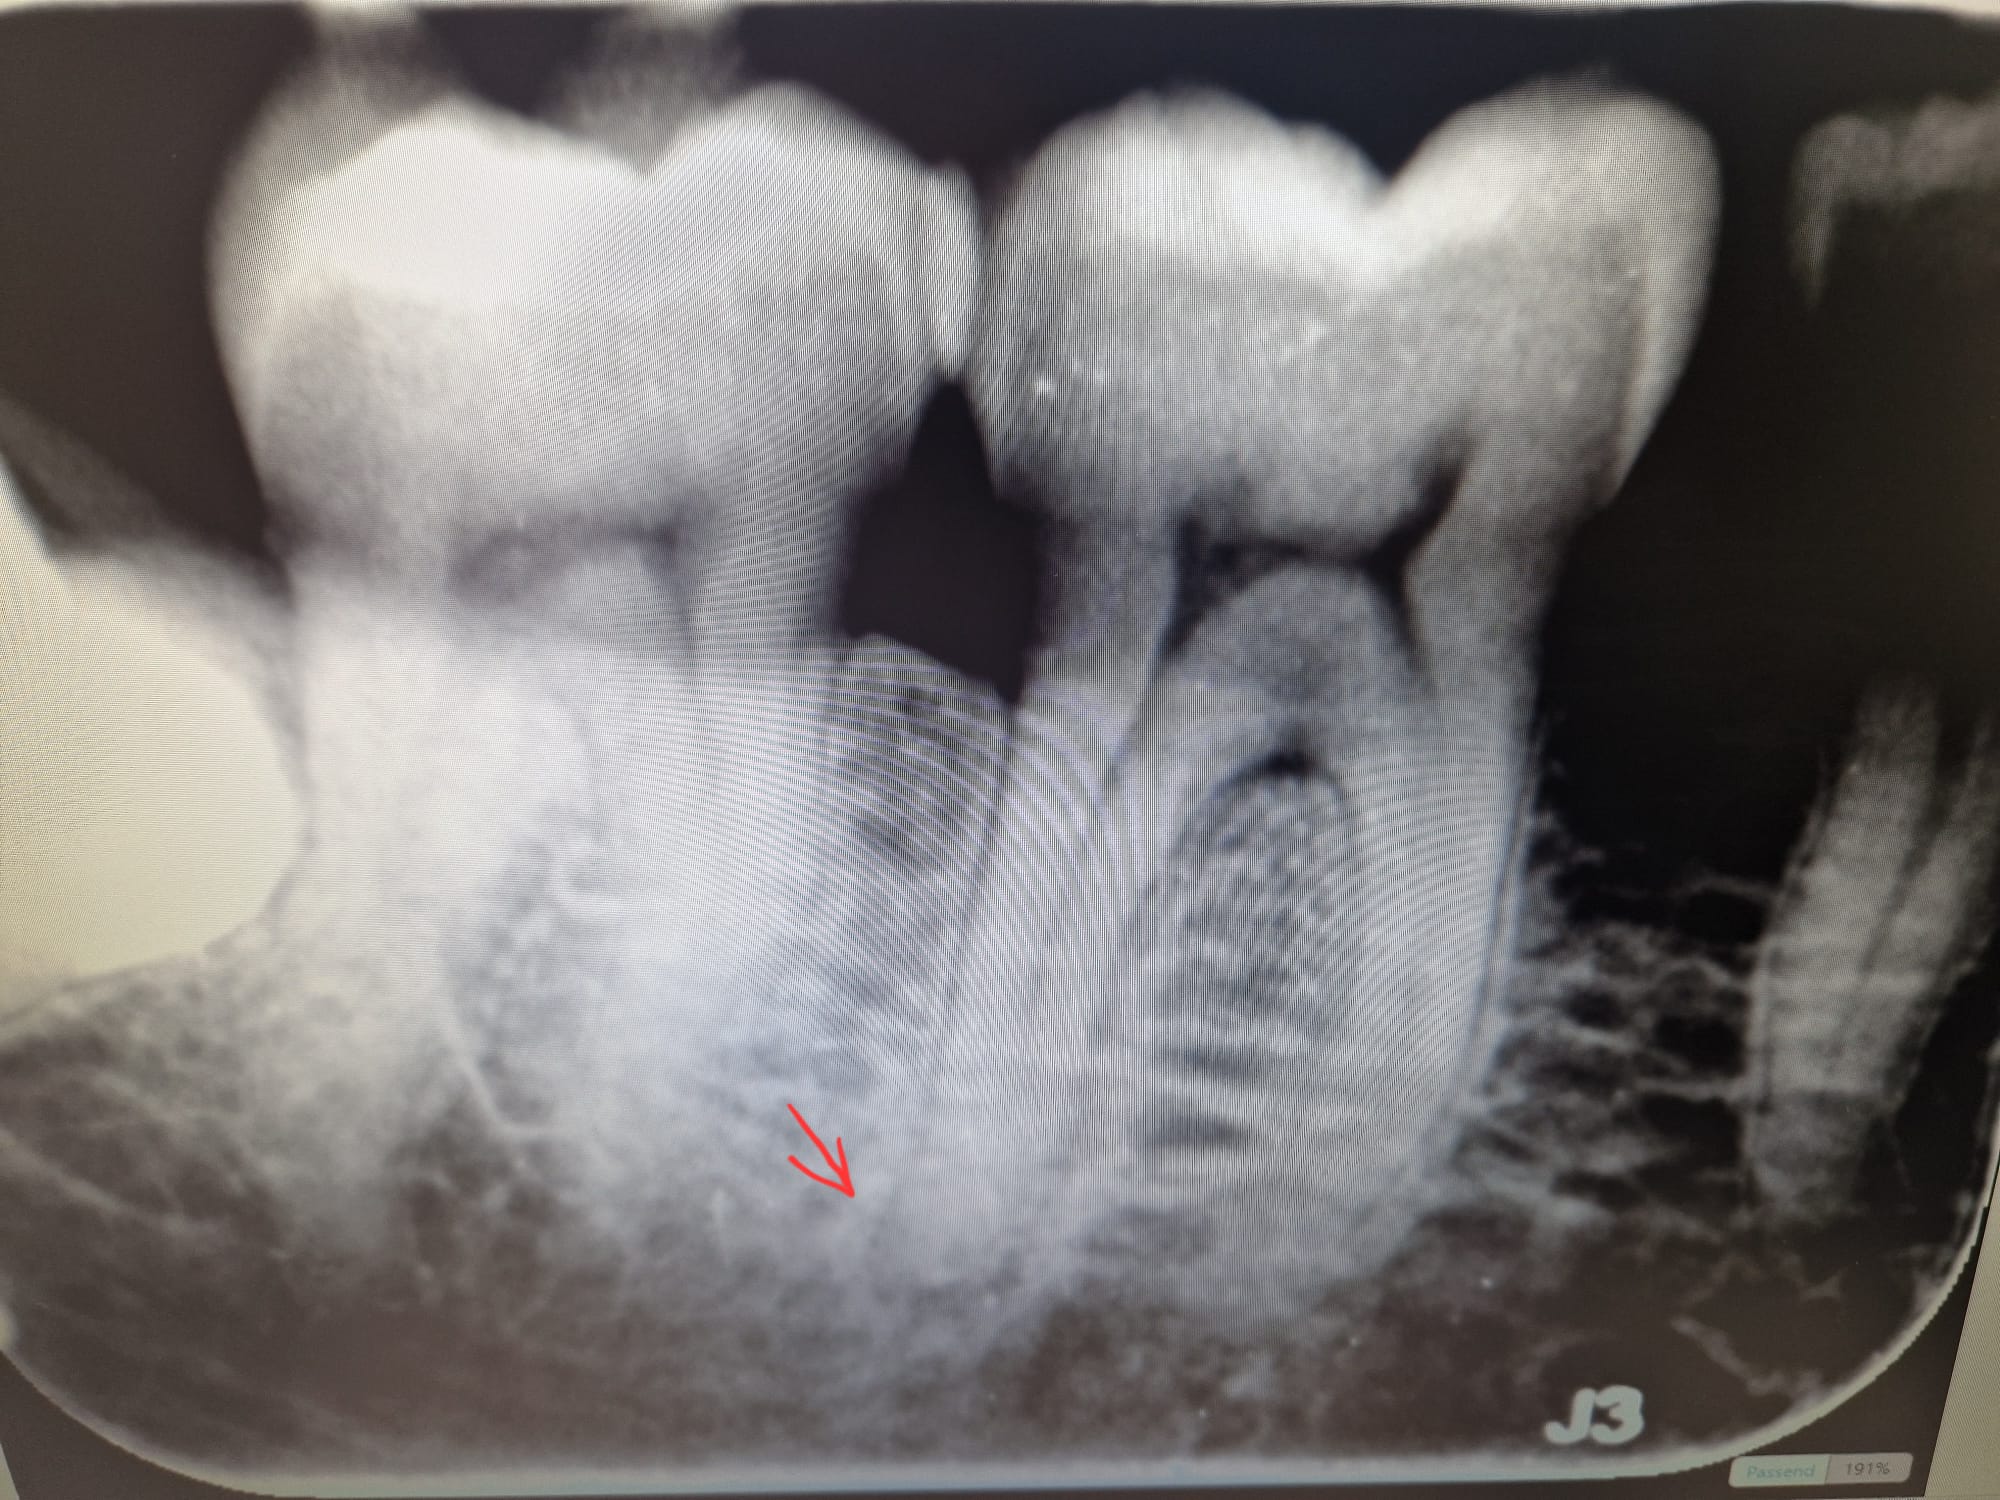

Geen duidelijke foto maar voor mij een groot gat (denk niet dat het sluiering is)in de 46 distaal(achterkant tussen de kiezen) daardoor zenuw waarschijnlijk afgestorven en ontsteking. Te zien aan de achterste wortelpunt. Maar ook flink botverlies tot voorbij de furcatie (wortelsplitsing). Wat gaat u met uw gebit doen?? hoe ziet de rest (li bo/onder) eruit. Afhankelijk daarvan beslissen of u hierin gaat investeren ( wortelkanaalbehandeling en later kroon, in combinatie met aanpakken bot verlies) of ander oplossing. Zou hier een extra foto willen zien ter verduidelijking.

bedankt voor uw reaktie. Ik heb helaas geen 2e foto. Ik heb een foto gemaakt van de rontgenfoto. Mijn tandarts weet niet goed wat te doen. Hij heeft er fluoride en gluma op gedaan, wat niet echt helpt. Het is nu wel iets rustiger. Hij gaat over een paar weken er composiet op doen op het blootliggend stuk. Verder heeft ij mij doorverwezen naar een endodontoloog omdat hij vermoed dat er een ontsteking bij de punt te zien is...

Neen ik zou echt een betere x-foto moeten beoordelen. Is de kies warm en koud gevoelig??. En wat bedoelt u met zenuwpijn?. Maar los daarvan.. Er is duidelijk bot verlies...Rookt U.? Denk dat endodontoloog een goed advies is als besloten wordt, in een algeheel behandelplan, tot behoud v die kies.Zijn er verdere X-foto's v uw gebit gemaakt?